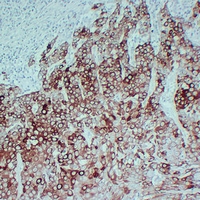

(Immunohistochemical analysis of Cytokeratin 17 staining in human lung squamous carcinoma formalin fixed paraffin embedded tissue section. The section was pre-treated using heat mediated antigen retrieval with sodium citrate buffer (pH 6.0). The section was then incubated with the antibody at room temperature and detected using an HRP conjugated compact polymer system. DAB was used as the chromogen. The section was then counterstained with haematoxylin and mounted with DPX.)